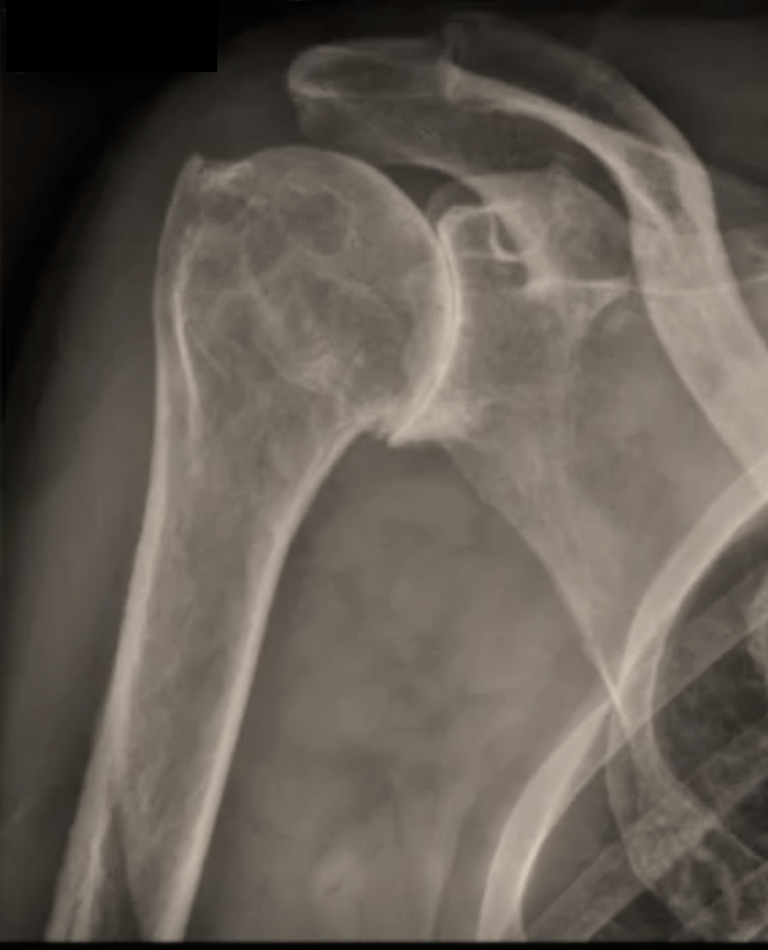

Vous présentez une arthrose de l'épaule / gléno-humérale ; ET une coiffe des rotateurs détériorée (1)

La conséquence est une omarthrose / usure excentrée de l'épaule ( 2).

Dans les forme évoluées, ou en cas d'échec du traitement médical, une prothèse totale d'épaule inversée est proposée.